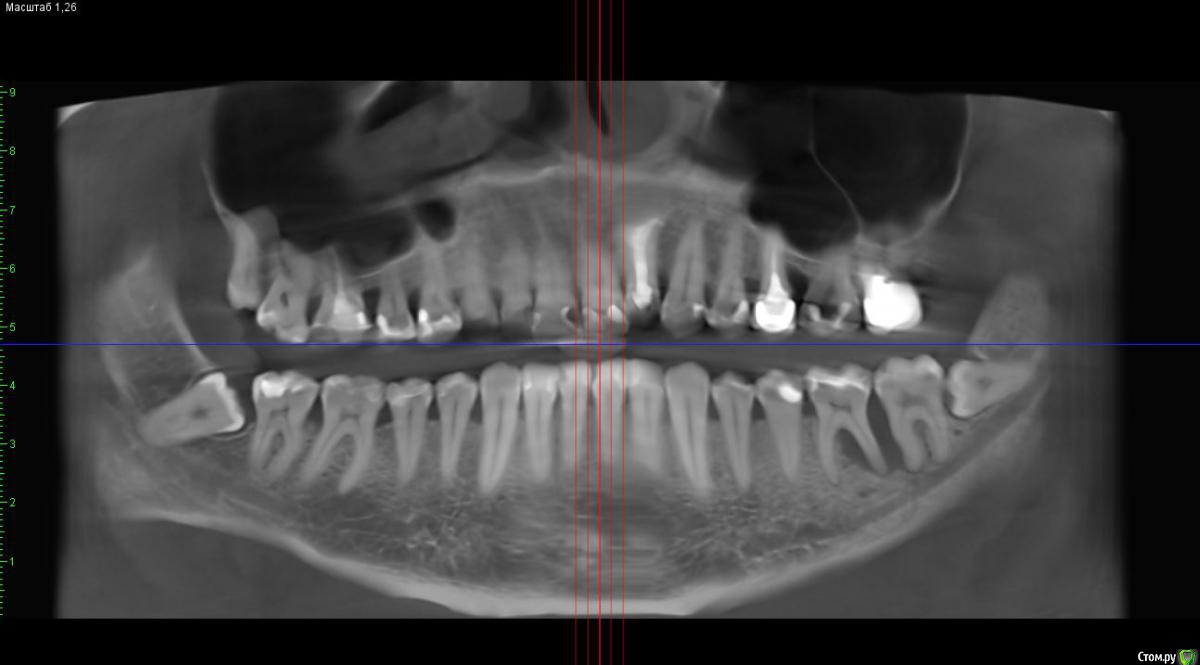

St. Опубликовано 19 февраля, 2018 Поделиться Опубликовано 19 февраля, 2018 Пациент 32лет, жалобы на боль в обл. 36-37 которую почувствовал вчера, ассиметрия лица. До этого не беспокоил никак, ни на температурные раздражители, ни на сладкое, ни на накусывание. В истории семейная предрасположенность к парадонтиту, соматически здоров.Пломбы на 36 37 нормальные, контакт есть, нависающих краев нет.Витальность не проверяли сегодня Пока хирург дал отток через карман и назначил антибиотики.Как вести дальше, какие шансы спасти 36? Ссылка на комментарий

St. Опубликовано 20 февраля, 2018 Автор Поделиться Опубликовано 20 февраля, 2018 Как прийдёт проверю.Кстати, подвижность 36 1 степени, 37 неподвижен.Вот панорама годичной давности. Карман был, но явно не такой. Ссылка на комментарий

St. Опубликовано 20 февраля, 2018 Автор Поделиться Опубликовано 20 февраля, 2018 Вроде бы с окклюзией все более менее, за исключением периодически растущих восьмерок.Кстати, а не могли ли они спроврцировать?Просто остальные карманы плюс минус на том же уровне последние 5 лет( сколько наблюдаю), а с этим обидно. До этого чистились регулярно, а это год не появлялся, но на чистки ходил регулярно.И вот те на подарочек! Ссылка на комментарий

Ximera Опубликовано 21 февраля, 2018 Поделиться Опубликовано 21 февраля, 2018 Я бы тоже проверила окклюзию (супраконтакты, при боковых движениях тоже), т.к. справа ситуация с пародонтом стабильная, а слева костные карманы, причем и сверху тоже.. Ну и восьмерки, конечно( Ссылка на комментарий